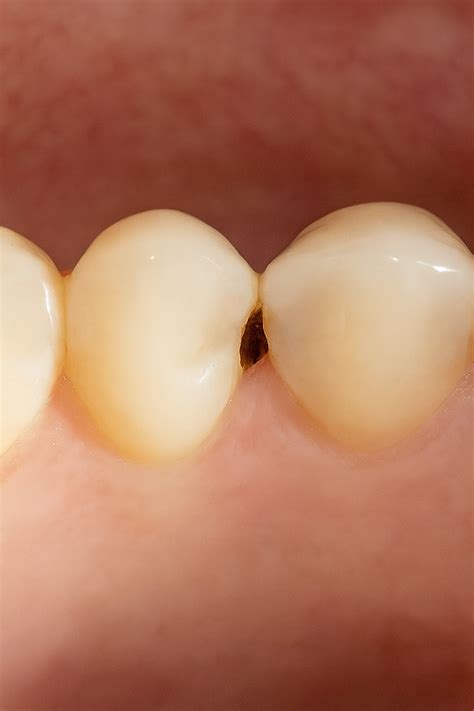

Visualmente, una caries pequeña puede no ser muy llamativa, pero hay características específicas que ayudan a identificarla. Además de las manchas blancas antes mencionadas, una caries en sus inicios suele mostrar cambios de coloración. En algunas ocasiones, la caries pequeña aparece como una pequeña cavidad o un hoyo en el diente. Estas cavidades son poco profundas al inicio y se localizan frecuentemente en los surcos de los molares o en las áreas cercanas a la línea de las encías en los dientes frontales.

La caries interproximal es aquella que se desarrolla en los espacios entre los dientes. Estas caries son más difíciles de detectar y, al afectar a más de un diente, son especialmente graves. Las personas con apiñamiento de dientes o que llevan ortodoncia o prótesis tienen más riesgo de padecer caries interproximales porque son más propensas a la acumulación de alimentos.

Las caries interdentales, también conocidas como caries interproximales, son aquellas que se desarrollan en los espacios entre los dientes, donde el cepillo dental no llega con facilidad. Estas caries se forman debido a la acumulación de placa bacteriana en zonas de difícil acceso.